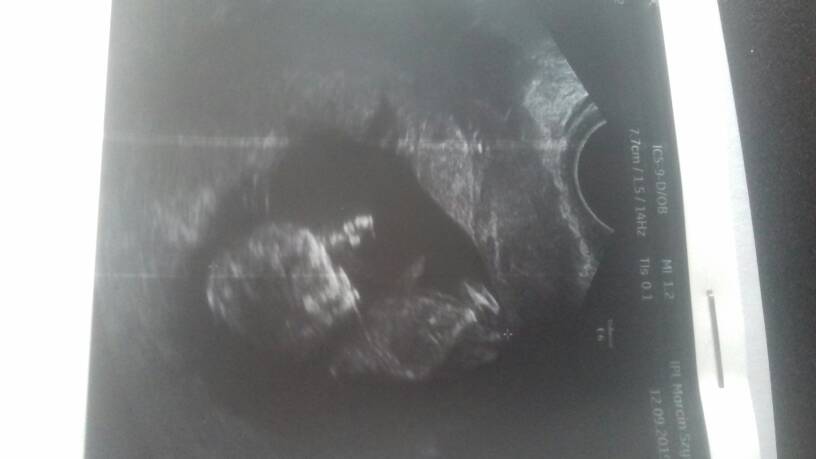

Maluszek ma 47cm 11t3d, serduszko bije 165bpm.

Przeziornosc karkowa 1.34 mm

Kość kosowa 1.27mm

Przeplywy wporzadku.

Nie zalecił żadbych dodatkowych badan gdyż ciąża rozwija sie prawidłowo[emoji5]Zobacz załącznik 1021645Zobacz załącznik 1021646Zobacz załącznik 1021647Zobacz załącznik 1021648